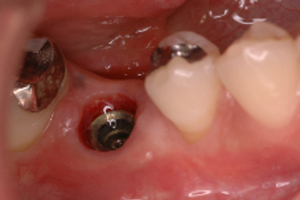

4.<インプラント1次手術>

骨の中にインプラント本体を植え、歯茎を閉じます。インプラントを植えること自体はさほど時間はかかりませんが、手術前にお口の中の清掃をしたり、レントゲンでインプラントを確認をしたり、手術後の全身状態の経過を診ますので、当日は十分な時間の余裕をみておいてください。

インプラントが骨と結合するのに3ヶ月ほど待ちます。

5.<インプラント2次手術>

インプラントが骨と結合した後、歯茎を貫通したふたを取り付けます。1回法の手術では最初の手術でそこまでしますので、2次手術は必要ありません。